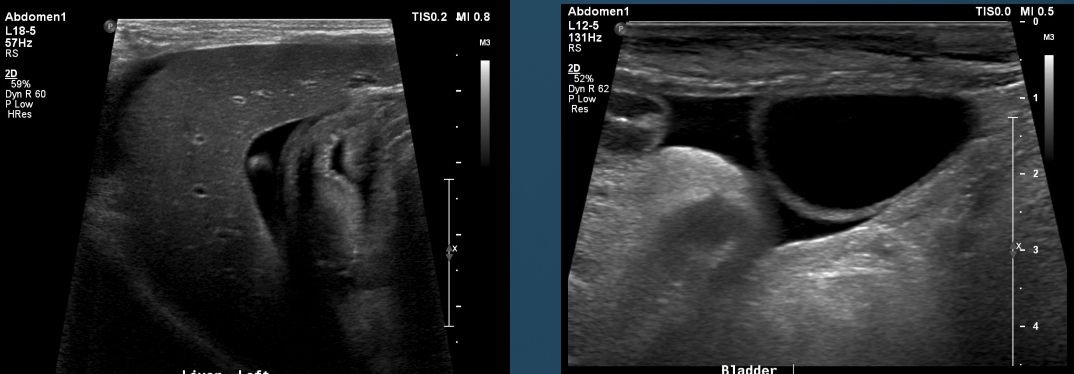

What is shown in these images?

anechoic effusion around liver (left) and bladder (right)